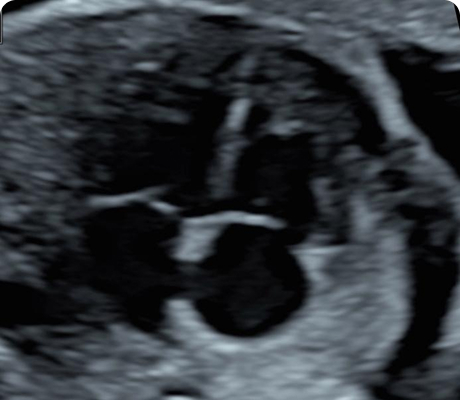

En la Clínica de Medicina Materno Fetal del Hospital Angeles Lomas, ofrecemos detección oportuna de enfermedades en el feto y complicaciones en la madre, mediante estudios de genética e imagen con tecnología avanzada y médicos altamente especializados.

"Durante el embarazo, los ultrasonidos son una parte fundamental del control prenatal. Nos permiten observar el desarrollo del bebé, identificar posibles complicaciones a tiempo y tomar decisiones médicas informadas para cuidar tu salud y la de tu bebé."